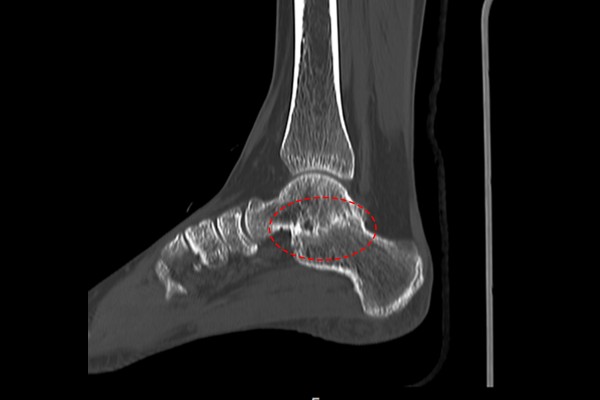

정상적인 우측 발에 비해 통증이 있는 좌측 발목은 거골하관절이 관절염이 온 것 처럼 좁아진 소견이 보였고, 정밀한 확인을 위해 CT검사를 추가로 시행하였습니다.

CT 검사 결과, 발목을 떠받치고 있는 거골과 발의 끝인 종골이 하나로 붙어있는 것이 확인되어 발 거종결합[거종유합,족근골융합](Talocalcaneal coalition)을 진단하였습니다.(거종결합의 증상은 발 내측 및 내측 복숭아뼈 아래쪽 통증이 흔하며, 심한분들은 바깥쪽 복숭아뼈 아래쪽으로 뒤꿈치가 아프다고 표현하십니다.)

거종결합이 확인되어, 환자분께서 말씀하셨던 복숭아뼈를 깎는 수술은 거종결합을 다시 2개의 뼈로 분리해주는 거골종골 분리술을 의도하고 시행하였던 수술로 추측됩니다. 다만 수술이 제대로 되지 않아 결합이 풀려있지 않았기 때문에 수술을 하고 나서도 3~4년 고생하고 계셨고, 저에게 발 중족골 골절 수술을 받으시고 좋은 결과로 건강한 일상을 되찾으셨던 환자분의 언니분께서 족부전문의인 저를 추천해주셔서 찾아오셨다 합니다.